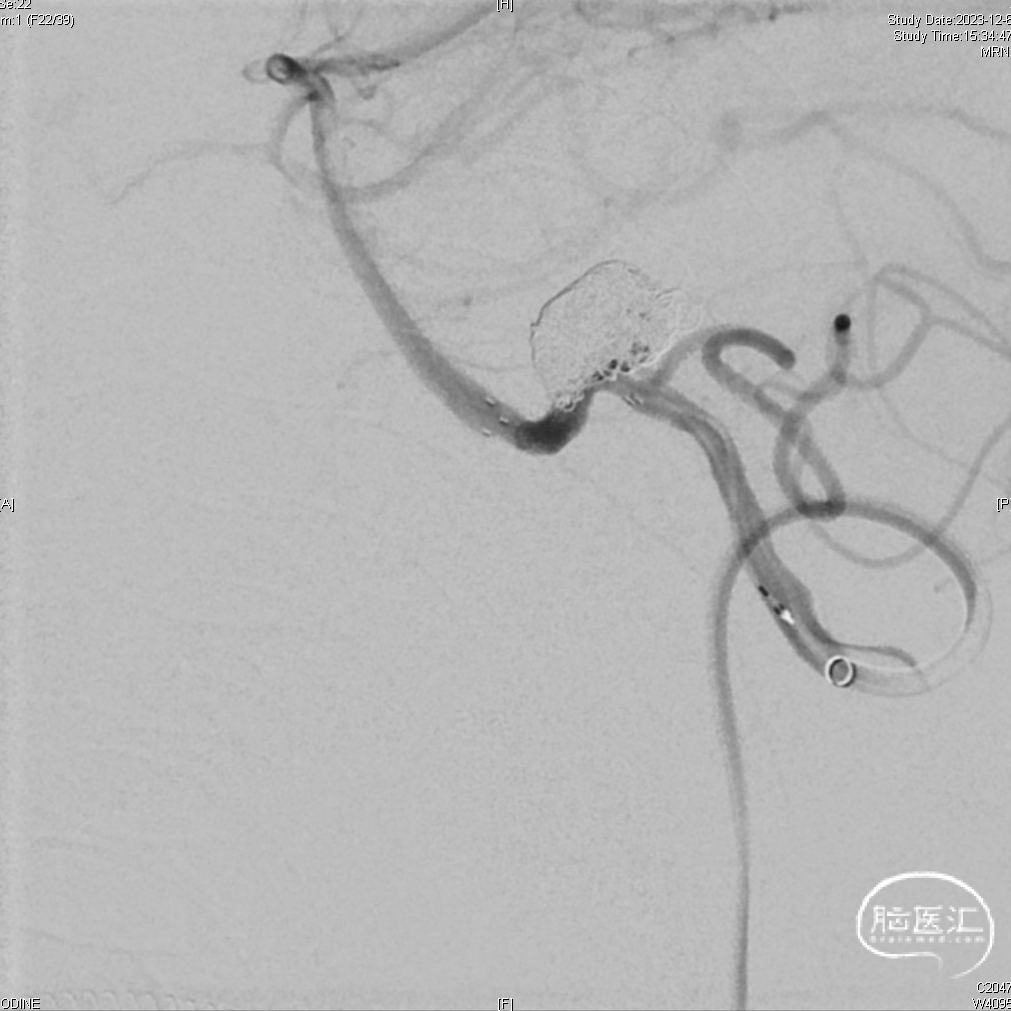

病变情况分析:术前DSA显示左侧PICA起始部动脉瘤,形态不规则,3D结果显示动脉瘤大小约为6.6*14mm,瘤颈宽6.2mm。

先将1枚弹簧圈释放于动脉瘤腔内不解脱,给予替罗非班抗血小板治疗,4.5*21mm支架横跨瘤颈成功释放,将支架微导管穿支架网眼置于动脉瘤内,双微导管技术填塞Jasper®弹簧圈及其他弹簧圈以实现致密栓塞。瘤腔填塞满意,载瘤动脉及远端分支通畅。

➢术后即刻造影

术后正位

术后侧位

1.小脑后下动脉(PICA)动脉瘤相对少见,约仅占颅内动脉瘤的0.5%~3%。发生于PICA的动脉瘤初次出血后,急性期再出血的发生率及Hunt-Hess级别较高,且再次出血的死亡率高,故对PICA动脉瘤破裂出血患者及时诊断与治疗非常重要。此例破裂动脉瘤位于椎动脉与PICA夹角处,与PICA关系密切,且左侧椎动脉为优势动脉(生命中枢脑干的最主要供血来源),所以必须首先保障PICA动脉的血流不受影响,并尽可能致密栓塞动脉瘤杜绝再出血风险,降低动脉瘤远期复发率。

2.术中应用了Tethys®中间导引导管到达V4段,稳定建立主体通路。并使用了一款“微构”设计的神经微导丝—DCwire™微导丝,在面对载瘤动脉血管成角近似90°时,表现出优异的扭控性及通过性,顺利引导支架微导管到位,以及帮助栓塞微导管轻松置入瘤腔,提高了手术通路建立的效率及手术的成功率。